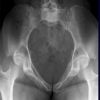

Becken tief a.-p.

Fraktur, Luxation, Z.n. Osteosynthesematerial

Symmetrisch und gleichmäßig gut belichtete Hüftgelenke und der Trochanteren. Trochanter major darf den Schenkelhals nicht überlagern und der Trochanter minor ist gerade erkennbar.